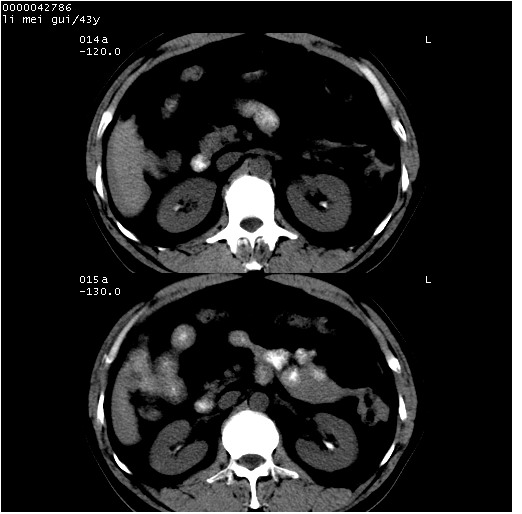

| 患者,男,43岁。突发腹痛2小时,面色苍白,难以平卧。自述近期无明确外伤史,为摩托车驾驶员。 腹部b超检查:脾脏中上极回声异常,肿瘤待排。 临床诊断:腹痛原因待查。 上中腹部ct轴位平扫+增强扫描(层厚10mm,螺距1.0,重建间隔10mm),图像如下: ![]() ![]() ![]() ![]() ![]() ![]() ![]() ![]() ![]() ![]() ![]() ![]() ![]() ![]() ![]() ![]() ![]() ![]() ![]() ![]() ![]() ![]() ![]() ![]() ![]() ![]() ![]() ![]() ![]() ![]() ![]() ![]() ![]() ![]() ![]() zrs发言:支持脾破裂 wwp发言:支持脾破裂并腹水。 xulianj发言:脾脏肿瘤破裂可能性大 zsl6918发言:不像肿瘤出血,考虑还是与外伤后引起的慢性出血有关 zzyy发言:平扫见肝周及脾周积液,脾内密度不均。脾内肿瘤较少见。还是外伤性脾破裂。 沈丘东方医院发言:脾门区一个不均匀强化病灶与其周液体相连多考虑脾占位破裂出血 yixianman001011发言:脾破裂并腹水是可以肯定的,具体原因多以肿瘤性破裂出血,脾脏淋巴瘤可能性大. 结果: 术后,经详细询问患者,其仔细回忆:一月前骑摩托时左侧腰部与别人有“轻微”触碰,因责任在自已,当时又无明显不适,未引起注意。 临床术后诊断:脾破裂并失血性休克(1.外伤性迟发性脾破裂。2.脾脏肿瘤破裂?) 术后标本病检:脾破裂并出血,未见明显肿瘤成份。 原贴地址:http://www.radinet.com.cn/forum_view.asp?forum_id=4&view_id=34070 |